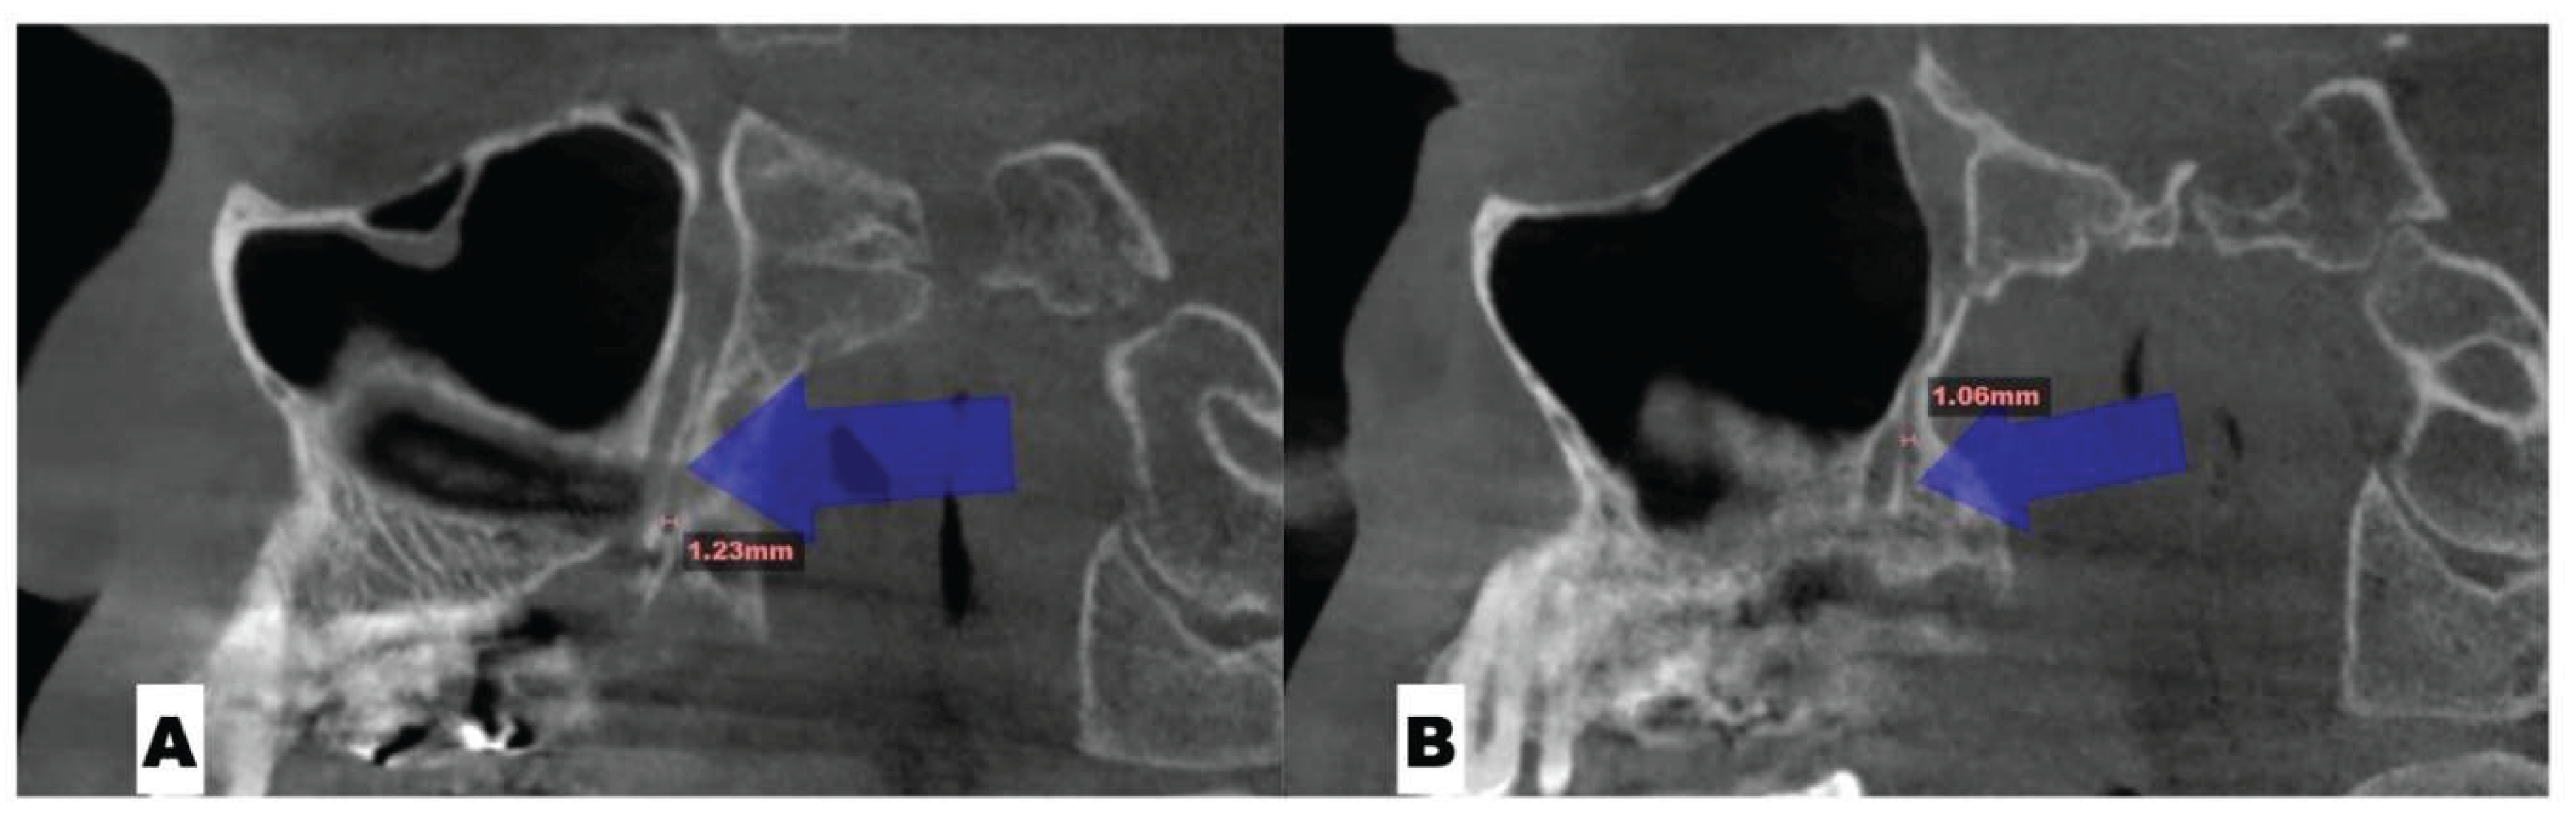

Background: While mini-screw-assisted rapid palatal expansion (MARPE) is effective for correcting maxillary transverse deficiency in adults, perimaxillary suture disarticulation—particularly at the pterygomaxillary junction—can be inconsistent. This study evaluates skeletal and dentoalveolar outcomes of a novel 3D-guided midpalatal piezocorticotomy-assisted MARPE protocol, focusing on expansion symmetry and pre-existing asymmetries. Methods: Three adult patients were retrospectively analyzed after treatment with 3D-guided midpalatal piezocorticotomy-assisted MARPE expansion and one with non-guided midpapalatal piezocorticotomy and MARPE expansion. Surgical guides were digitally designed using CBCT data to align with the nasal septum orientation in multiple planes. Perimaxillary suture disarticulation was measured pre- and post-expansion, and dentoalveolar changes were evaluated. Post-expansion asymmetries were addressed using directly printed aligners. Results: Complete midpalatal suture separation (mean 8.48 mm), involving both anterior and posterior nasal spine regions, was achieved in one patient. Bilateral pterygomaxillary disarticulation averaged 1.06–1.23 mm, resulting in forward–outward rotation of the nasomaxillary complex. Additional separation occurred at the frontonasal (2.03 mm) and vomeromaxillary (1–2 mm) sutures, with no significant changes in orbital or peri-orbital sutures. One patient presented with pre-existing dentoalveolar asymmetry, which intensified the perceived post-expansion imbalance but was successfully corrected with directly printed aligners. In the second case, 5.6 mm of suture separation resulted in a limited lateral nasal width increase (<1.5 mm), while maxillary base expansion exceeded 6 mm. A significant canine plane cant (1.2 mm) and divergent axial inclinations of the maxillary central incisors relative to the palatal plane were also observed. In the second case, a non-impactful palatal bone fracture with asymmetric displacement of the left palatine fragment was documented. After 16 months of aligner therapy, all cases exhibited favorable remodeling of the palatal structures, midpalatal suture, and alveolar processes, accompanied by improved dental alignment, occlusal plane symmetry, and mandibular dentoalveolar adaptation. The dento-alveolar expansion achieved in the third case over the course of 16 months of treatment was approximated at 4 mm. The fourth case showed consistent improvement with direct printed aligners after MARPE midpalatal diasrticulation of 11 mm after experiencing minor bone fracture. Conclusions: Human skulls exhibit considerable variability between the left and right sides, which can influence spatial balance. Pre-existing cranial asymmetries appear to be the primary contributors to asymmetry following MARPE treatment. Careful evaluation of dentoalveolar discrepancies and axial tooth inclinations is essential for preventing and managing potential asymmetric dental arch outcomes during the post-expansion phase. Although peri-maxillary bone fractures are relatively uncommon, their occurrence is influenced by multiple factors. Adjunctive techniques, such as 3D-guided midpalatal piezocorticotomy, show promise in significantly lowering the risk of intra-expansion peri-maxillary fractures.

| Pterygomaxillary | 1.06-1.23 mm |